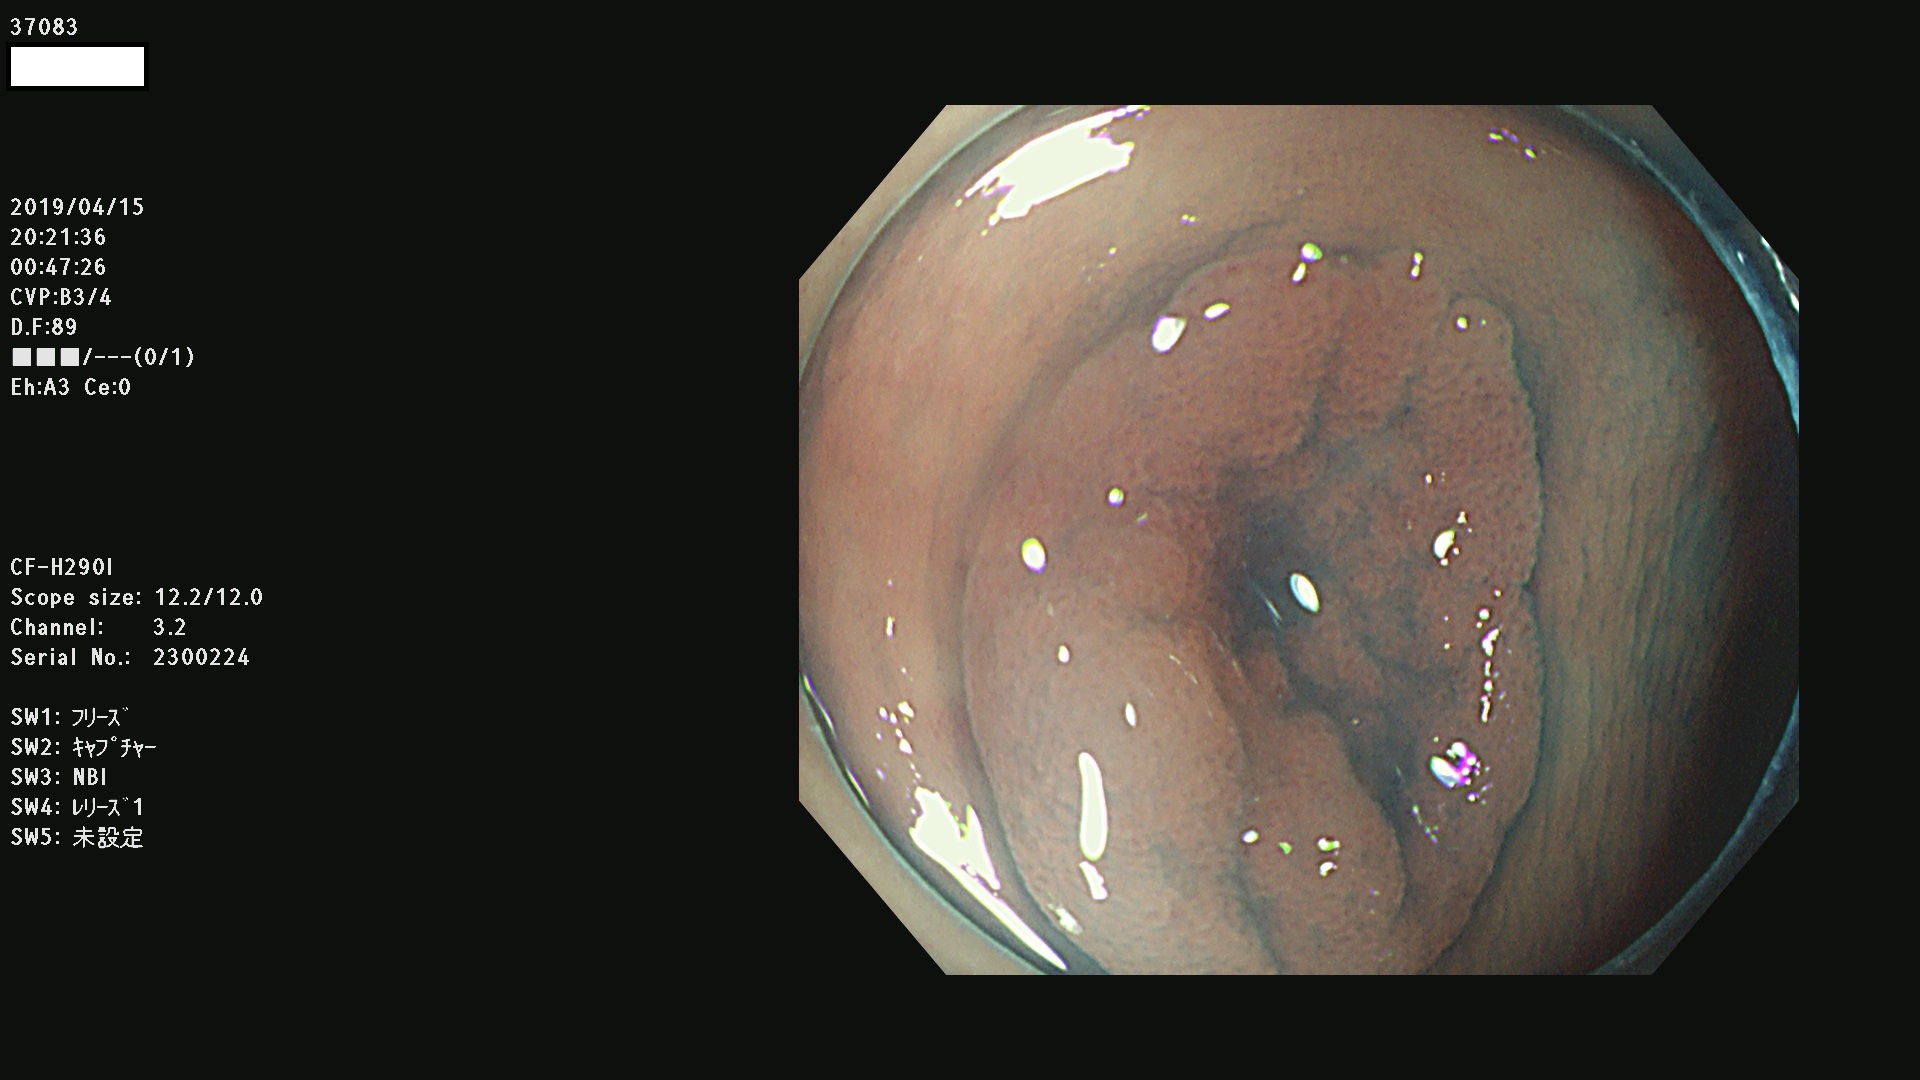

37000 37002 37004 37005 37006(SSAPのみ) 37007 37009 37013 37014 37015 37017(SSAPのみ) 37019 37020 37021 37022 37025 37026 37027 37028 37029 37031 37032 37033 37034 37035 37036 37037 37038 37041 37042 37043 37044 37045 37047 37051 37052 37053(SSAPのみ) 37055 37056 37058 37060 37061 37062 37063 37067 37072 37073 37074 37076 37077 37078 37079 37080 37081 37083 37084 37085(SSAPのみ) 37086 37087 37088 37089 37092 37093 37094 37095 37097 37098 3709

発見困難で危険性の高い平坦型病変(上記100名より抽出)